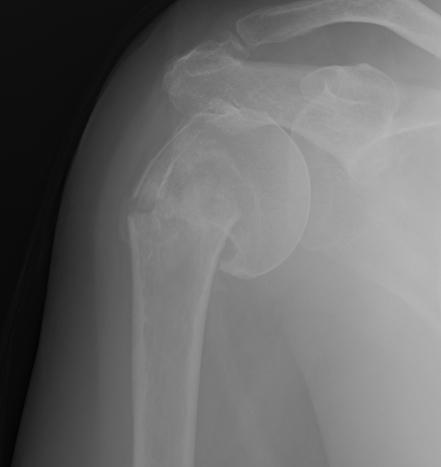

proximal humerus fracture Background ORIF with locking plate Arthroplasty Greater tuberosity fractures Lesser tuberosity fractures / avulsions Book traversal links for Proximal humerus fractures ‹ Pectoralis Major Tears Up Background ›